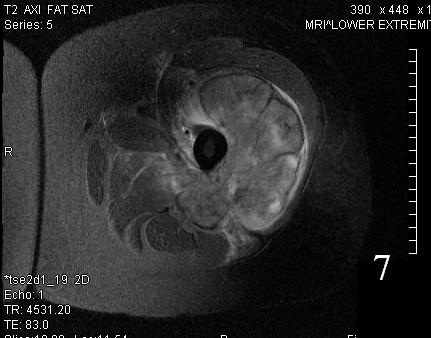

GENERAL INFORMATION Tumoral calcinosis is a very rare entity, characterized by large tumorlike calcium deposits and painless mass, arising near to the articular soft tissue areas. Common areas affected are elbows, hips, knees rarely involve hands and feet. No obvious...